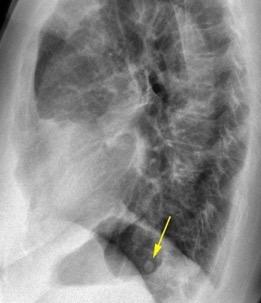

Rotura esofágica

Laceración transmural espontánea.

Excesos en comida y/o bebida

Marzo 2014: Perforación longitudinal distal secundaria a episodio de vómito (síndrome de Boerhaave). Derrame pleural izdo. que evoluciona a empiema.

Wang C-T et al. Tension hydropneumothorax in a Boerhaave syndrome patient: A case report . World J Emerg Med, 2021. Katabathina V et al. Nonvascular, nontraumatic mediastinal emergencies in adults:a comprehensive review of imaging findings. Radiographics. 2011.